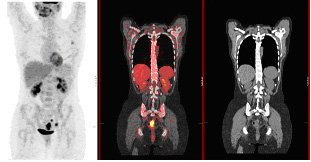

• Clinical PET/CT

Establishing a clinical protocolClinical applicationsArtefacts and normal variantsClinical Imaging with 68Ga PET - Radiopharmaceuticals and Therapy